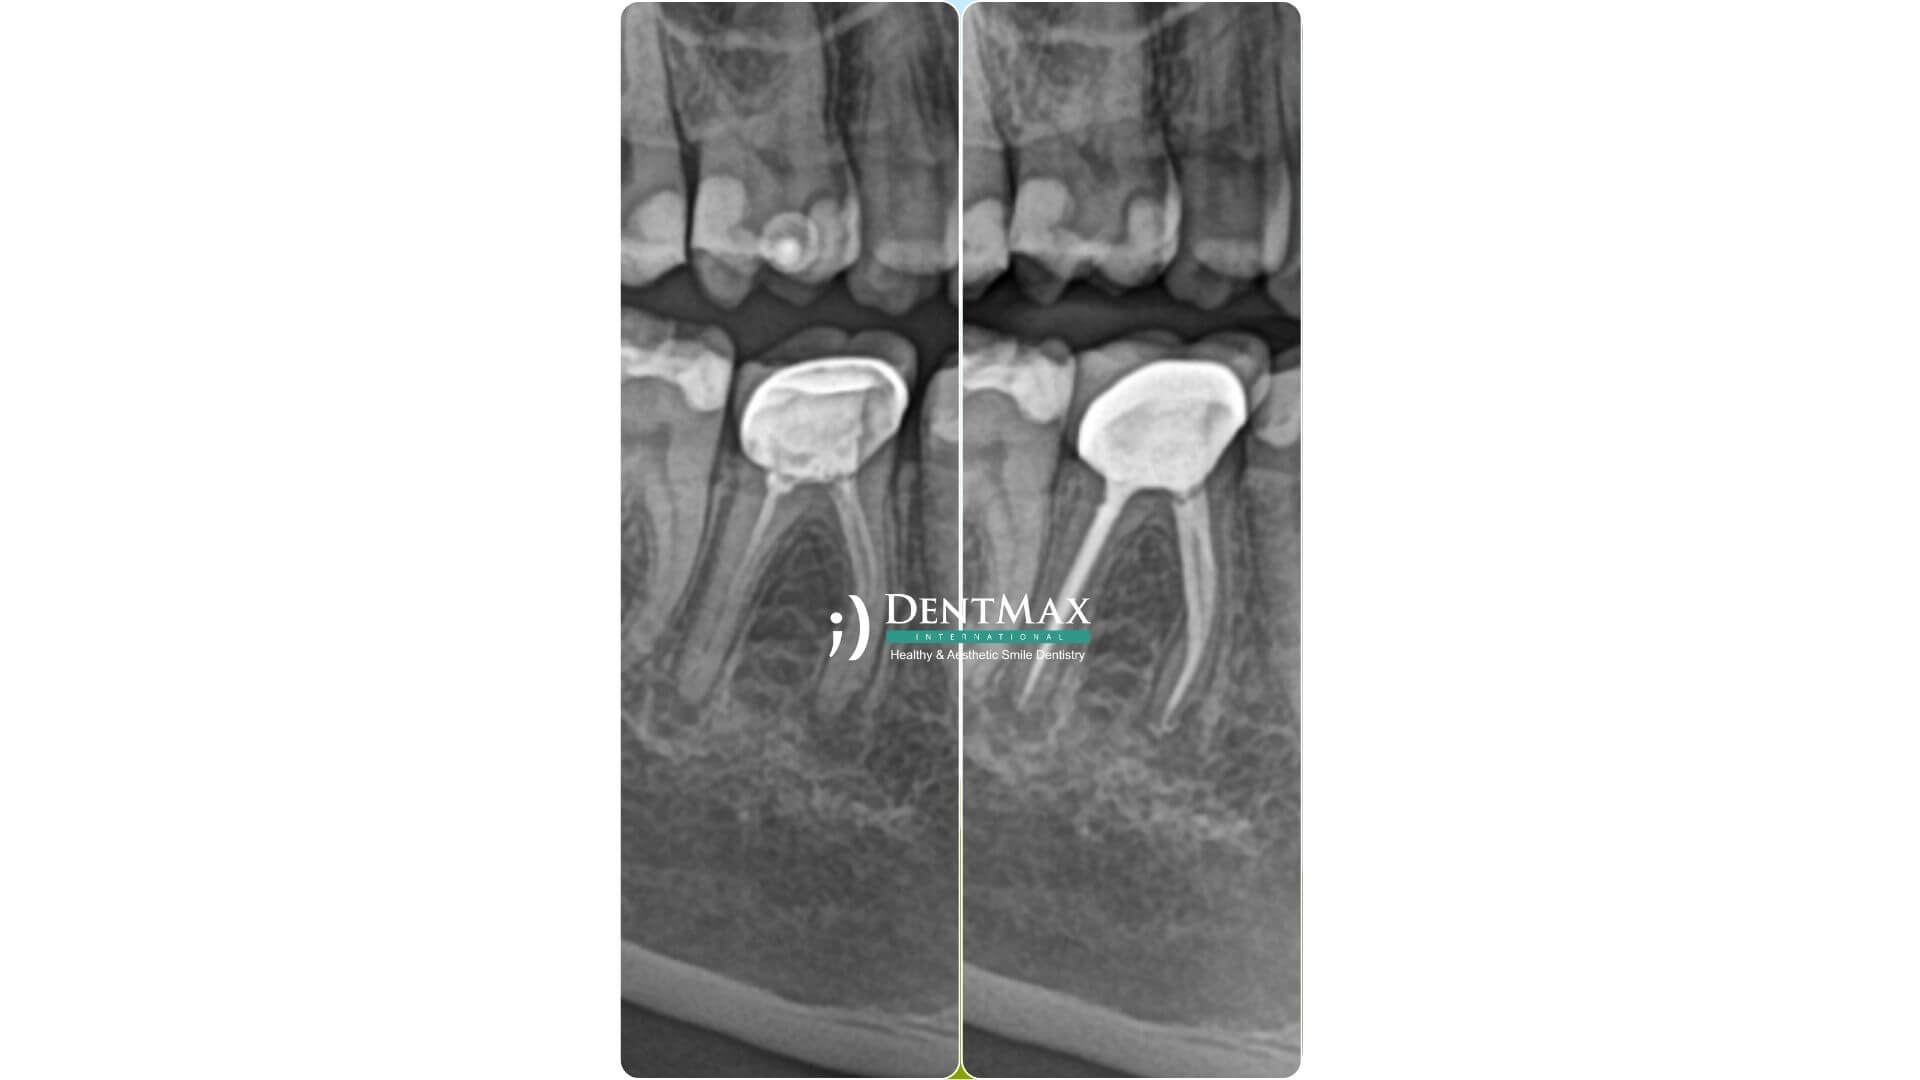

Lorsqu’une dent déjà traitée par canal développe une nouvelle infection ou une douleur persistante, un retraitement endodontique peut être nécessaire. Il consiste à retirer l’ancienne obturation, nettoyer les canaux et les refermer correctement. À la Clinique DentMax Istanbul, nous réalisons ces procédures avec précision grâce à la technologie endodontique moderne. Retrouvez ici toutes les informations sur le déroulement et les bénéfices du retraitement.

Il s'agit d’un second traitement du canal dentaire sur une dent déjà traitée auparavant mais dont l’infection est revenue ou la guérison n’a pas été complète. Le matériau est retiré, les canaux sont nettoyés et désinfectés, puis rebouchés.

L’ancienne obturation est retirée avec des instruments spécifiques. Sous microscope, les canaux sont nettoyés et désinfectés. Une obturation temporaire est posée, puis une définitive selon l’évolution.